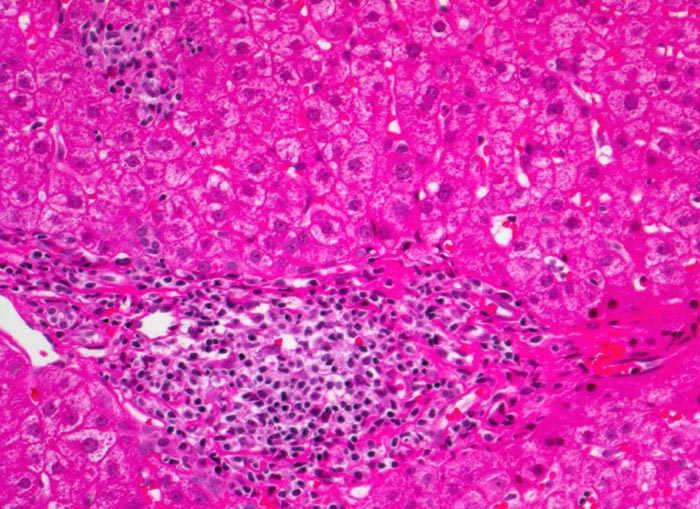

• Dichte mononukleäre portale und lobuläre Entzündungsinfiltrate mit Ausbildung von Lymphfollikeln in den Portalfeldern.

• Übergreifen der Entzündung auf das Parenchym (=Interface oder Grenzzonenhepatitis).

• Abgerundete hypereosinophile apoptotische Hepatozyten (Councilman-Körperchen).

• Geringe Portalfeldfibrose. Das sollte der Kliniker dem Pathologen mitteilen: